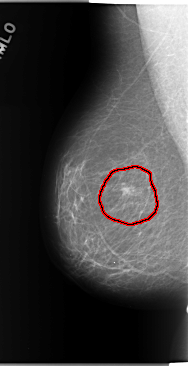

FILE: C_0143_1.RIGHT_CC.OVERLAY

TOTAL_ABNORMALITIES 1

ABNORMALITY 1

LESION_TYPE MASS SHAPE ROUND MARGINS SPICULATED

ASSESSMENT 5

SUBTLETY 5

PATHOLOGY MALIGNANT

TOTAL_OUTLINES 1

BOUNDARY